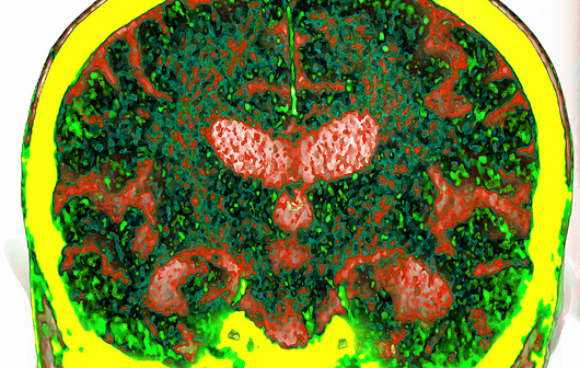

تتميّز أمراض دماغيّة كثيرة مثل الزهايمر وباركنسون، من ضمن ميزات أخرى، بخللٍ في أداءٍ الحاجز الدّمويّ الدّماغيّ. قد تُؤدّي الالتهابات الموضعيّة لدى مرضى الزهايمر مثلًا إلى زيادة نفاذيّة الأوعيّة الدّمويّة في الدّماغ، ويؤدّي ذلك إلى ردود فعل الجهاز المناعيّ التي قد تُؤثِّر في تقدُّم المرض. على الرّغم من ذلك، من الضروريّ استخدام الأدوية لعلاج الأمراض الدّماغية في كثير من الحالات، والتأكُّد من وصولها إلى المكان المناسب من خلال الدّورة الدّمويّة. لن تستطيع الأدوية الوصول إلى الهدف (المكان المناسب في الدّماغ)، لأنّ الحاجز الدّمويّ الدّماغيّ لا يتيح مرور الجزيئات الكبيرة من خلاله. يجعل هذا الوضع من علاج الأمراض والأورام السرطانيّة في الدّماغ مهمةً صعبةً للغاية.

يتضرّر النشاط السّليم للحاجز الدّمويّ الدّماغيّ عند حصول الأمراض الدّماغيّة المختلفة. مسح CT لِدماغ مريض الزهايمر | المصدر: Vsevolod Zviryk, Science Photo Library